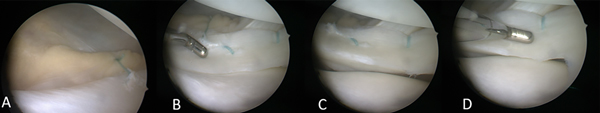

Figura 3: Rodilla izquierda. A) Visión artroscópica del menisco externo. B) Exploración sistemática del menisco externo con palpador en su cara femoral. C) Exploración de la cara tibial, se constata ojal más amplio de lo habitual. D) Inestabilidad y subluxación hacia anterior.

Las cirugías fueron efectuadas por el mismo equipo quirúrgico (HR, CC, MM). En primer lugar, se realizó la artroscopía en la que se confirmó el diagnóstico de menisco externo hipermóvil por desinserción meniscocapsular posterior, con lesión de ligamentos meniscales (meniscos capsulares) posteriores, también se constató la calidad del menisco, tratando de buscar un patrón lesional artroscópico (ver fig. 3). Luego se cruentaron los bordes de la lesión y se realizó su reparación-sutura con sistema todo-adentro Meniscal Cynch™ (Arthrex, EE. UU.), y en algunos casos, a demanda, se combinó con técnica afuera-adentro, utilizando el remanente de la sutura meniscal todo-adentro Fiberwire® 2.0, con puntos verticales. Posteriormente a la fijación meniscal se verificó su estabilidad utilizando el palpador, con movimientos de flexión y extensión bajo control artroscópico. En todos los casos se constató un menisco firme y estable (figs. 4 y 5).

Figura 5: A) Rodilla derecha. Desinserción posterior del menisco externo, luxable hacia anterior, muy inestable. B) Inestabilidad meniscal externa, con desplazamiento del tercio posterior casi en contacto con el tercio anterior. C) Visión final de la reparación y estabilización meniscal, se colocaron tres puntos verticales con sistema todo-adentro Meniscal Cynch™ por detrás del tendón del poplíteo combinado con un punto vertical con Fiberwire® 2.0, con técnica afuera-adentro por delante del tendón del poplíteo.